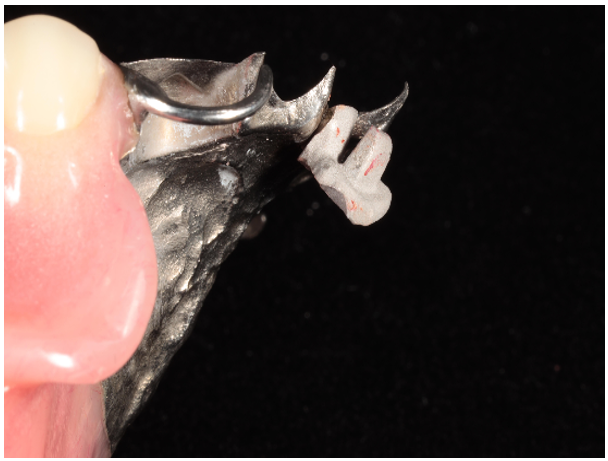

Due to the reflective properties of the metal base obturator, an alginate impression was made of the obturator in the patient’s mouth. After the impression set, the impression and the patient’s obturator were removed and poured in type IV dental stone while still combined After a retentive groove, palatal to site #9, was created in the RPD framework, the existing obturator and fabricated cast were coated with scanning spray (Scanspray, Renfert, USA) and scanned using an extraoral scanner (EOS) (inEos X5, Dentsply Sirona, USA). Digital scan of the opposing arch, and a buccal bite registration were also obtained using the same EOS. A custom abutment was designed in CAD software (Exocad), milled from wax, and cast in ticonium. Once the abutment was divested, it was seated into the retentive groove created in the framework and laser welded into place using an AlphaLaser ALP50 (Figs. 2 and 3).

Figure 2: Soldered abutment on obturator framework.